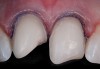

Fig 1. Preoperative (Fig 1), preparation (Fig 2), and final postoperative (Fig 3) images of a two-unit CL-I feldspathic veneer case.

Figure 1

Fig 2. Preoperative (Fig 1), preparation (Fig 2), and final postoperative (Fig 3) images of a two-unit CL-I feldspathic veneer case.

Figure 2

Fig 3. Preoperative (Fig 1), preparation (Fig 2), and final postoperative (Fig 3) images of a two-unit CL-I feldspathic veneer case.

Figure 3